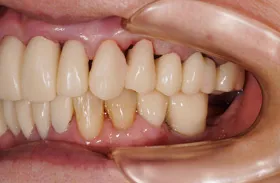

他院で「歯槽膿漏は治らない」と言われ、当院にご来院されました。歯が乱ぐいのため、歯並びもよくしたい、下は歯を既に失っているので噛めるようにもなりたい、またコーラスをされていて人前で口をあけることが多いので、できるだけ見た目を意識した治療をしてほしいとのご要望でした。

■治療(仮歯装着)後